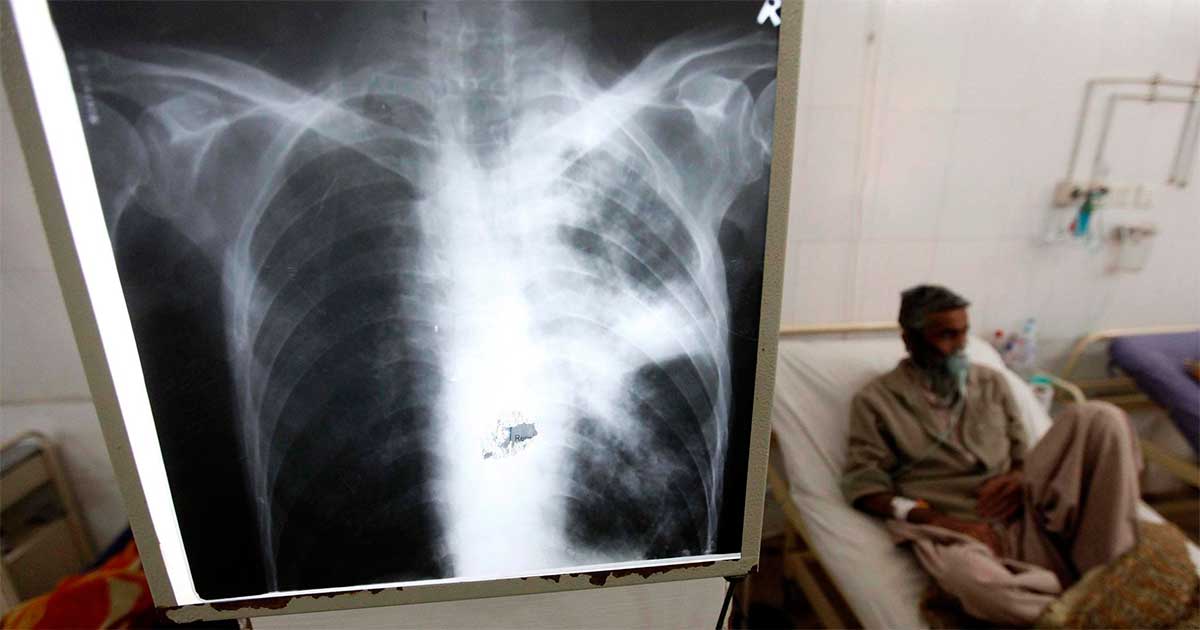

Ginebra.- Millones de vidas están en peligro debido a la interrupción de la ayuda internacional de Estados Unidos para la lucha contra la tuberculosis, especialmente en países de bajos ingresos que casi dependían totalmente de ella para combatir una de las enfermedades infecciosas más letales, advirtió este miércoles la Organización Mundial de la Salud (OMS).

La interrupción de la ayuda, subrayó la OMS, pone en especial riesgo a 18 países de las regiones más afectadas (África, Sureste Asiático y Asia Oriental-Pacífico), que dependían en un 89% de la ayuda estadounidense.

La OMS recuerda que los programas de prevención, tests y tratamientos contra la tuberculosis han salvado unos 79 millones de vidas en los últimos 20 años, y reconoce que gran parte del progreso "ha sido impulsado por la ayuda exterior a países en desarrollo, particularmente de USAID".

Aunque la OMS no lanza previsiones sobre las vidas que podrían perderse ante los recortes, recuerda que durante la pandemia de covid-19 las interrupciones de servicios de atención a la tuberculosis provocaron un exceso en el número de muertes promedio de unas 700 mil personas entre 2020 y 2023.